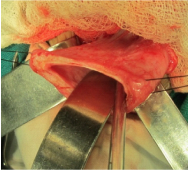

Investigations revealed anaemia, leucocytosis, deranged electrolytes and metabolic acidosis. USG was suggestive of a suspicious obturator hernia on right side. CT scan was suggestive of bulging of a large complex cystic structure with air-fluid level on the right side. Sagittal reformations also suggested the inferior descent of the cystic structure through the perineal floor (Figures 4 &5). The deranged laboratory parameters were corrected and the child was taken for emergency exploration. Intra-operatively, it was found that the massive hydrocolpos was protruding through the perineum as the bulge. There was no perineal or obturator defect. Drainage of the massive hydrocolpos was done by an abdominal vaginostomy (Figures 6&7).

Figure 6 Intra-operative Images.

Figure 7 Intra-operative Images.